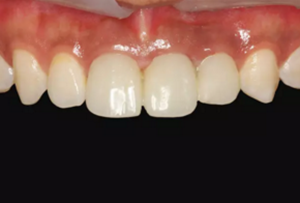

圖1 術(shù)前微笑像

圖2 術(shù)前口內(nèi)像

圖14 術(shù)后4個月口內(nèi)像

圖16 軟組織成形后口內(nèi)像

圖23 最終修復(fù)后即刻口內(nèi)像

圖25 最終修復(fù)后復(fù)查口內(nèi)像